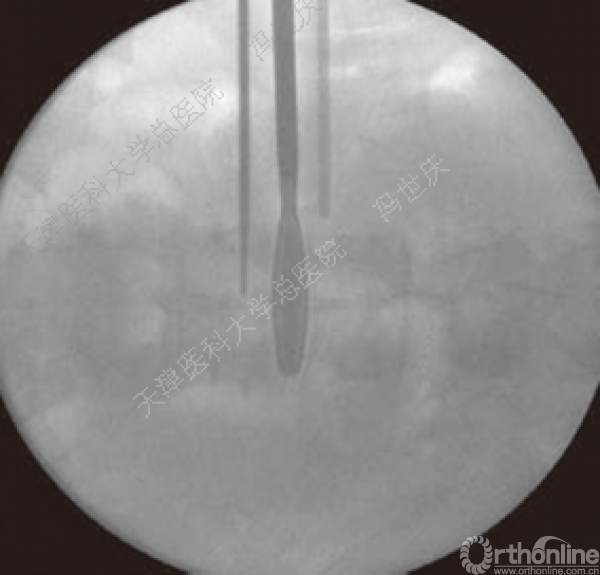

刨刀位于正中

刨刀清扫终板